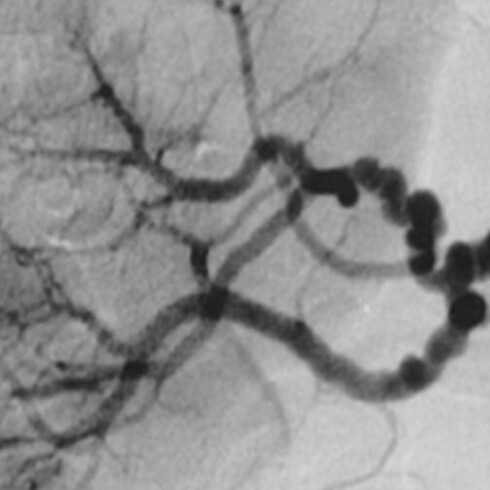

A Dios gracias, eso faltaba a la verdad. Cuando el cirujano doctor lo describió, me alegré. Un aneurisma es una falla congénita que puede suceder a cualquier edad. Es difícil de sanar, toma tiempo (mucho tiempo) y yo no contaba con ese preciado tesoro a mis 64 años.

No lo sabía aún, pero sufrí un hematoma subdural, en una de las tres capas que protegen el cerebro. No había caído en cuenta de un sangrado invisible crónico y nunca se me ocurrió pedir una resonancia.